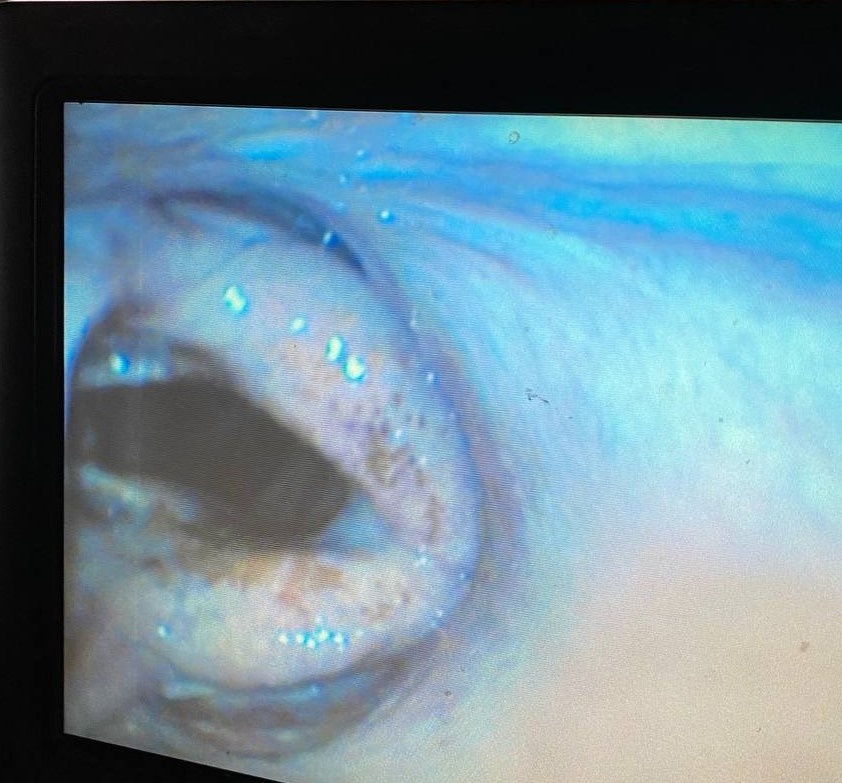

Клинический случай из практики Мобильного конного госпиталя MAXIMA VET: у лошади кашель, выделения из ноздрей, ответ на лечение не долгосрочный.

При эндоскопии ВДП выявлена поднадгортанная киста, нарушение глотания и аспирация кормового содержания в трахею.

Поднадгортанная киста формируется из остатка эмбриологического щитовидно-язычного отростка, чаще всего они врожденные, редко бывают приобретенными вследствие воспаления и травмы.

Рекомендуется хирургическое лечение данной патологии.